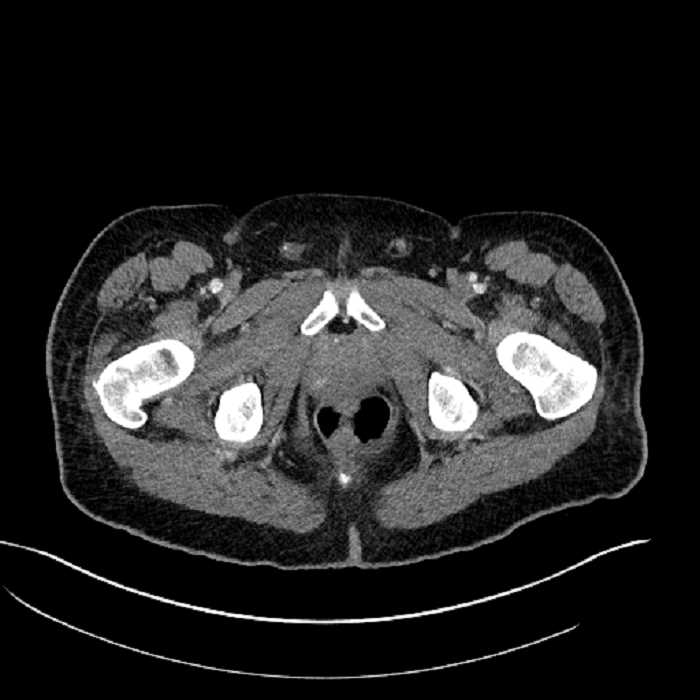

• Mild mural thickening of a segment of the sigmoid colon with adjacent fat stranding and a 1.5 cm fluid and gas collection along the tip of an inflamed diverticulum

• Loss of the normal fat plane between this collection and adjacent loops of small bowel, which demonstrate mural thickening

• High grade stenosis of the left common iliac artery, with the left internal and external iliac arteries remaining patent

• Ankylosis of both sacroiliac joints

Acute sigmoid diverticulitis complicated by a small contained perforation and a large abscess in the right hepatic lobe. Additional small subcapsular abscesses along the anterior margin of the left hepatic lobe.

Additionally, loss of the normal fat plane between the peridiverticular collection and adjacent thickened loops of small bowel raises the potential for an enterocolonic fistula.

High grade stenosis of the left common iliac artery. The left external and internal iliac arteries are patent.

Hepatic abscess showing the double target sign with low density internally surrounded by a thin inner enhancing rim (red arrow) and ill-defined outer low density rim (yellow arrow). Blue arrow indicates an internal septation. Red arrows: additional smaller subcapsular abscesses. Red arrow: focal contained perforation associated with diverticulitis.